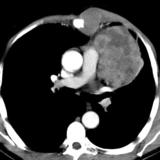

Case 9 Thymoma CT

Date: 04/04/2010

Views: 3594